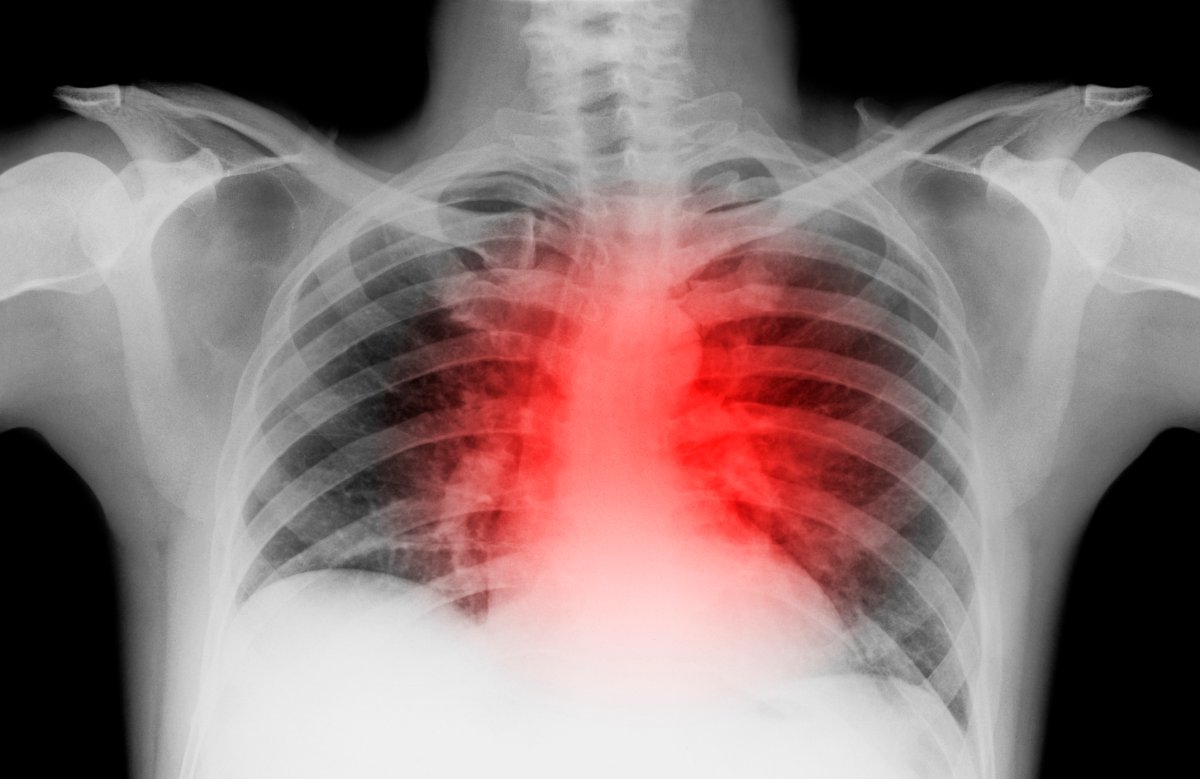

COVID-19 Vaccines Can Cause Sudden Cardiac Deaths: Warns Expert, Calls For Its Withdrawal From Market

Joseph Fraiman said that he and his team have multiple autopsy studies that provide 'essentially conclusive evidence' that all the mRNA COVID-19 vaccines are inducing sudden cardiac deaths.